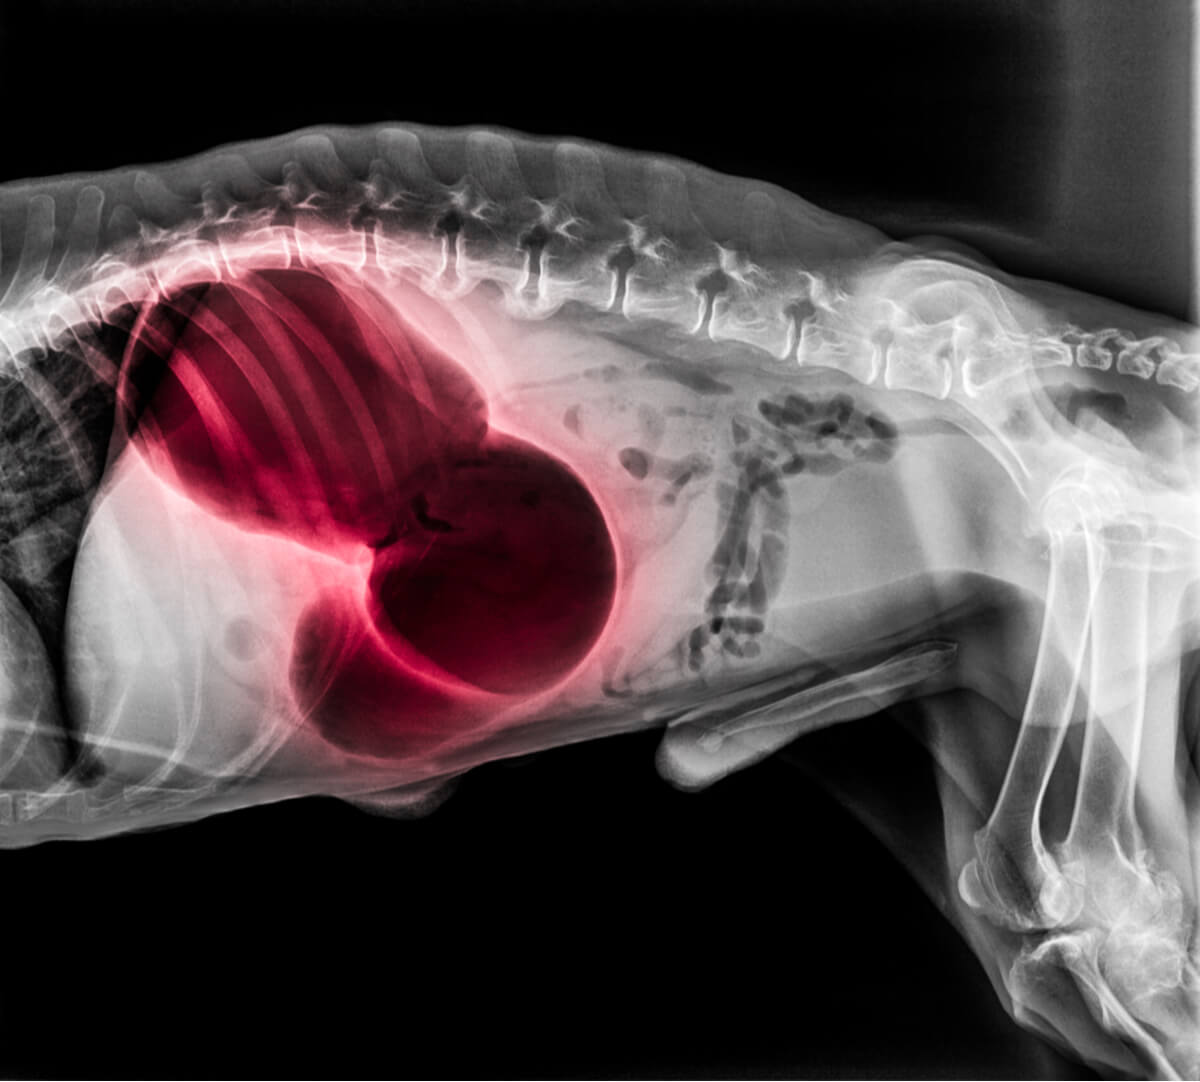

4. Tumori nel tratto gastrointestinale

Sfortunatamente, neanche i cani sono immuni dal cancro. In ogni caso, questo evento clinico è molto raro, poiché il cancro allo stomaco rappresenta meno dell’1% delle neoplasie maligne nei cani. Inoltre, queste patologie di solito compaiono quando il cane ha già un’età piuttosto avanzata, tra i 6 ei 9 anni.

I cani con tumori nel tratto gastrointestinale possono mostrare feci sanguinolente, difficoltà a defecare, dolore addominale e persino una massa tumorale palpabile al tatto. A seconda del tipo di tumore, le possibilità di guarigione possono essere molto elevate o quasi nulle.